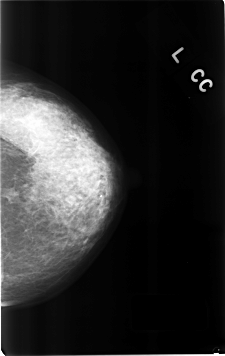

C_0314_1.LEFT_CC

LEFT_CC LINES 4624 PIXELS_PER_LINE 2920 BITS_PER_PIXEL 12 RESOLUTION 50 NON_OVERLAY